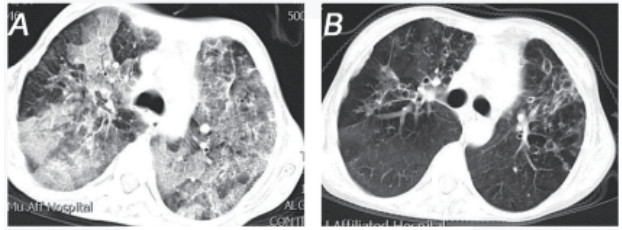

| A、B为患者在同样CT设备,同样扫描厚度,同一影像序列(280)腹部正位CT图像。A:患者入院腹部CT,提示巨脾,脾脏最大径为136.000 mm,体积是1 755.064 mm3;B:患者复查腹部CT,脾脏最大径为104.000 mm,体积是641.545 mm3。 图 2 患者腹部CT图像 |

患者女,31岁,因“咳嗽、咳痰伴腹胀3 d”于2019年2月4日转诊至遵义医科大学附属医院。入院前3 d,患者咳嗽、咳痰,发热39℃,伴腹胀、腹痛,就诊当地医院,考虑“肺部感染、脾大”,予抗感染治疗,无好转遂转院。患者既往史、个人史及流行病学史无特殊。查体:呼吸34次/min,体温39 ℃。双肺闻及湿性啰音,左腹部及脐周压痛,肋缘下10 cm触及脾脏,越过前正中线。胸部CT示支气管扩张并双肺感染,腹部CT示巨脾,体积1 755.064 mm3。白细胞(WBC)2.24×109/L,红细胞(RBC)2.71×1012/L,血小板(PLT)67×109/L,C反应蛋白(CRP)73.60 mg/L。入院诊断:(1)脓毒症、支气管扩张并感染;(2)三系(WBC、RBC、PLT)减少,原因:脾功能亢进;(3)巨脾。诊断依据:(1)患者临床表现及病史;(2)检查、检验结果;(3)sepsis 3.0,SOFA评分大于2分;(4)结核检测及胸部CT排除结核分枝杆菌感染,骨髓穿刺结果不支持血液及淋巴系统疾病,回顾患者既往病史及腹部CT图像排除肝硬化等疾病。多学科会诊:针对巨脾,考虑脓毒症所致充血性肿大,不考虑肝硬化及班替氏综合征,继续抗感染治疗, 菌培养+药敏结果提示哌拉西林舒巴坦钠、盐酸莫西沙星敏感的金黄色葡萄球菌,最终诊断:(1)脓毒症;(2)支气管扩张并感染;(3)巨脾;三系减少病因:脾功能亢进。再次根据药敏试验调整抗生素,患者体温恢复正常,脾脏体积出院时仅有641.545 mm3, 三系终于恢复正常范围,感染指标下降,好转出院。